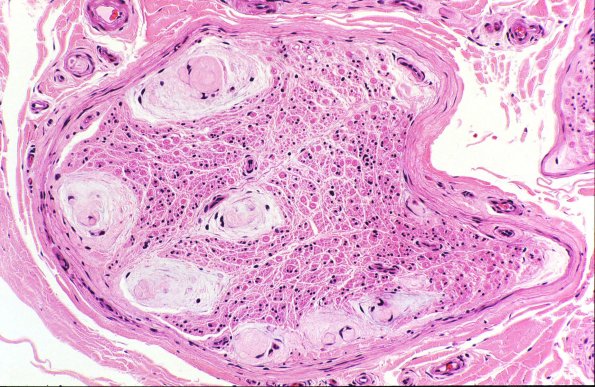

Numerous Renaut bodies in a patient with no history of compression or hypothyroidism. (H&E)